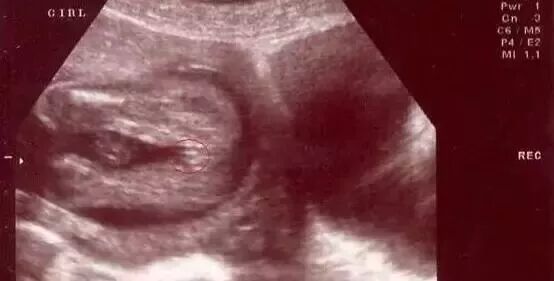

第五种:男宝女宝四维彩超图有不同特征

男宝:"凸出的东西" 是他的标记:如果看到圆圆的是蛋蛋,如果看到圆圆的加小肠的就是全部JJ。

女宝:三条白线是明显的女宝特征,如果没有看到明显的三条白线,就看两腿之间有没有突出的东东,且中间有小凹槽的,就是女宝。